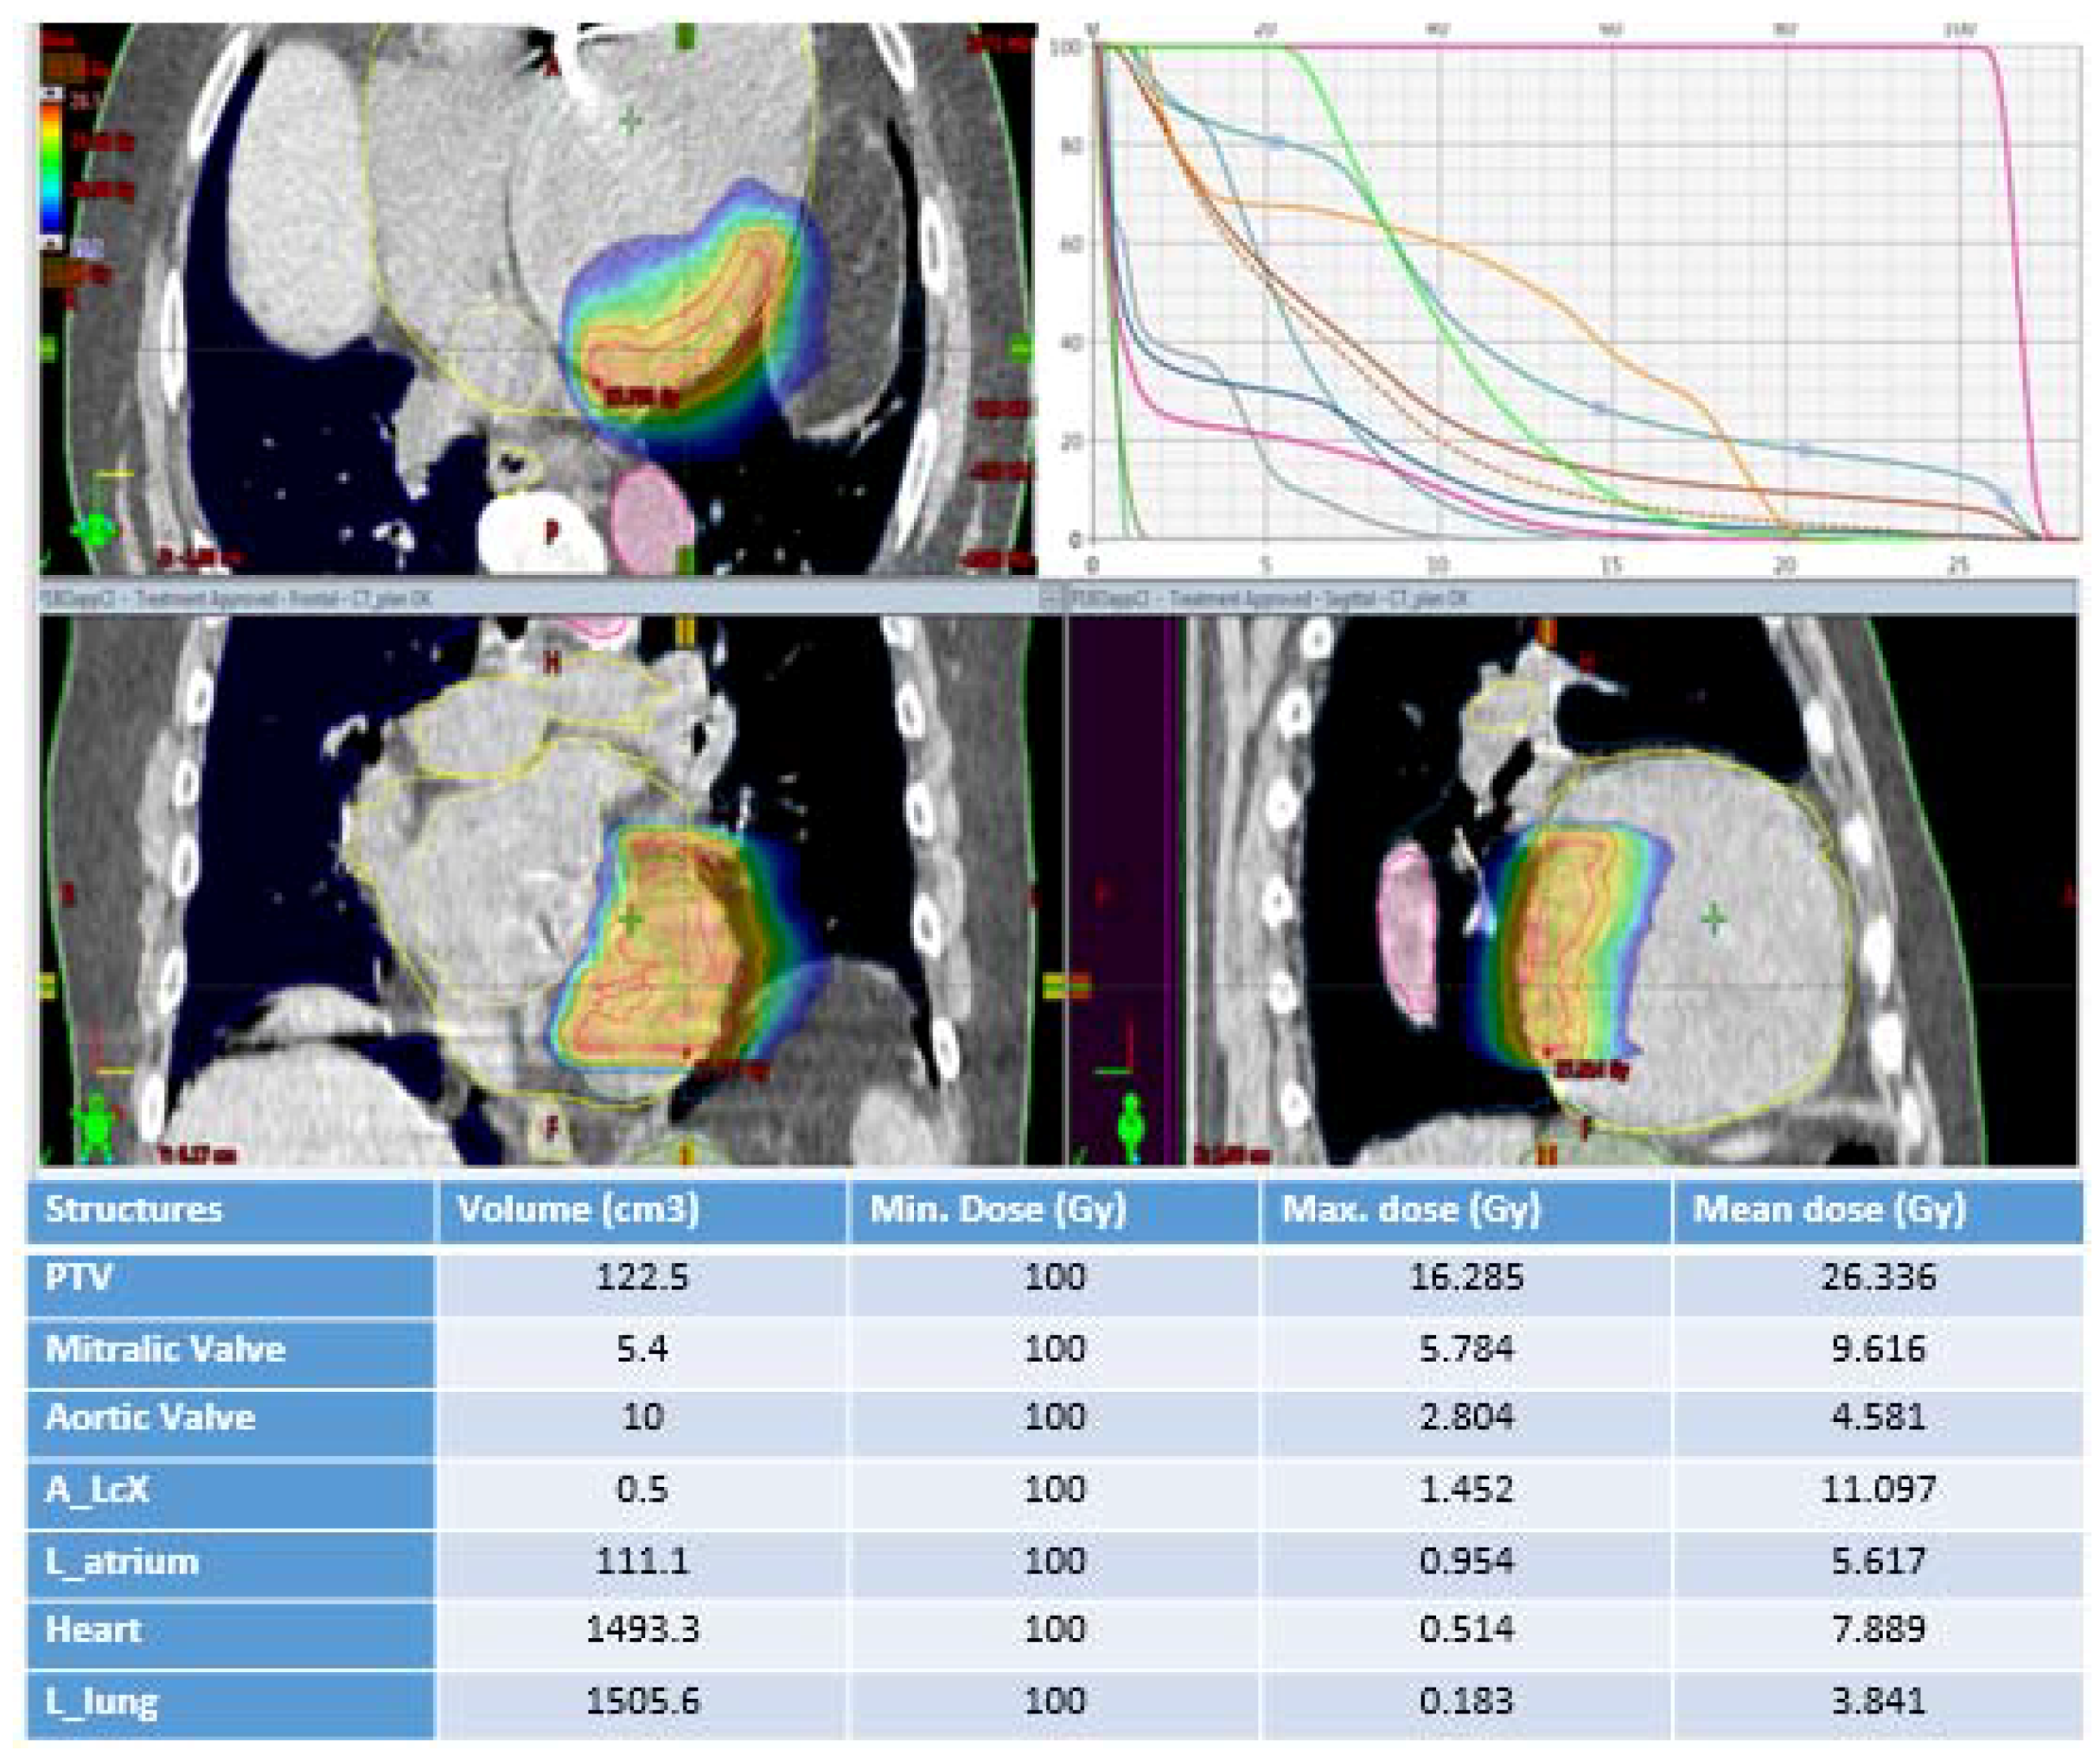

4. Treatment Planning and Treatment Delivery

| Present study | R | 1 | M | 81 | 25 | 122.5 | 6 | immediate | none |